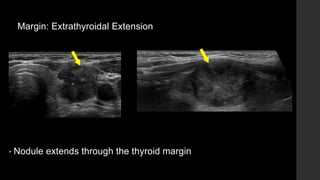

Margin: Extrathyroidal Extension

• Nodule extends through the thyroid margin